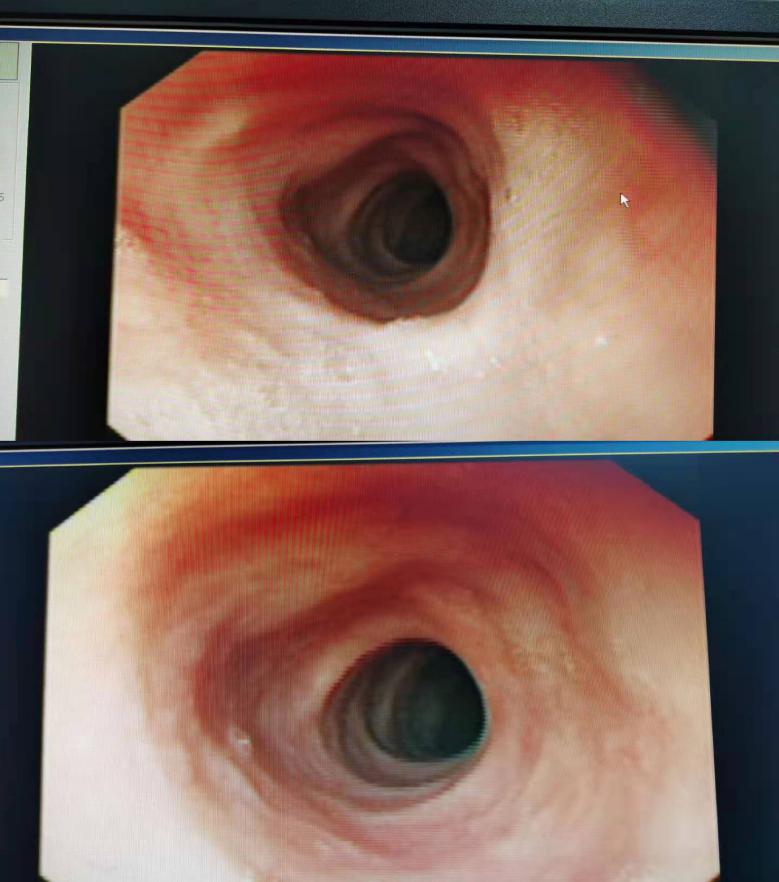

术后4个月复查胃镜的情况

刘鹏主任介绍,彭阿姨患的是食管上段早期癌症,ESD术实施全周剥离,十分成功,食管早癌全周型的患者,术后极易出现食管狭窄,需要再次手术扩张食管,而彭阿姨术后四个月复查的胃镜显示,食管恢复正常,未出现狭窄。